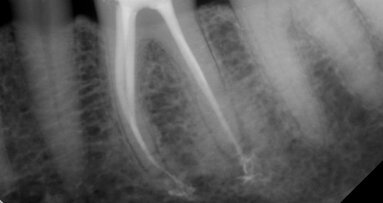

Despite wide global acceptance of rotary nickel-titanium (RNT) canal enlargement, hand files remain central to endodontic practice. It can be argued ...